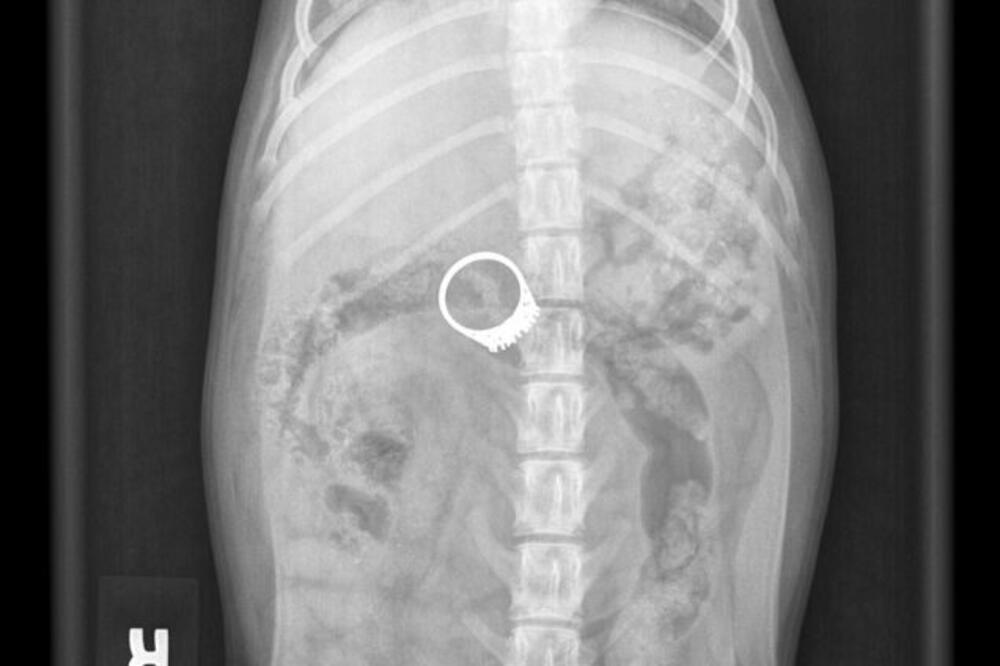

Britanka Karen Vuli je kupila metalni detektor kako bi tražila svoj metalni prsten koji je odjednom nestao sa stola iz njene dnevne sobe.

I našla ga je, gle čuda, u svom šestomjesečnom kučetu Barniju.

Karen je duže vrijeme sumnjala da je upravo njen kućni ljubimac “smazao” prsten sa stola, a detektor je pištanjem potvrdio njene sumnje.

Kako piše britanski Metro, žena je psa odmah odvela kod veterinara gdje su odmah izveli hirurški zahvat kako bi ukonili prsten star skoro 100 godina.

“Taj prsten je mogao da ga košta života. Sva sreća da sam kupila detektor”, kazala je Karen.

Veterinarka je savjetovala Karen, ali i sve vlasnike kučića da drže sitnije predmete podalje od životinja. Barni se trenutno oporavlja kod kuće.